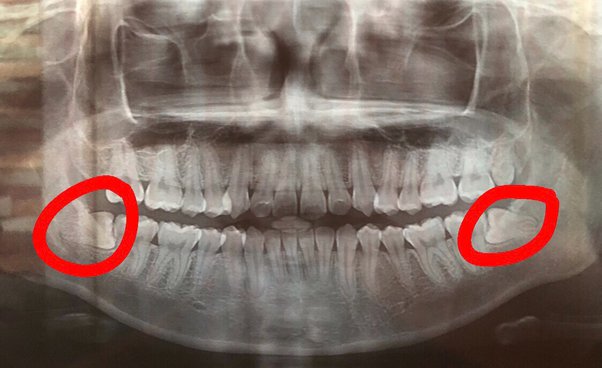

X-Ray Gigi Panoramik

Nah ini yang paling “wah” kelihatannya.

Sekali foto, semua gigi dan rahang kelihatan.

Biasanya dipakai buat:

• Cek gigi bungsu

• Perencanaan behel

• Evaluasi rahang

Dan jujur, ini yang bikin aku paling takjub.

Baru sadar ternyata posisi gigi di dalam itu kompleks banget.